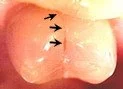

Cracked tooth. When a tooth is cracked, a filling will not seal the crack. A crown has to be placed over the tooth to hold it and the crack together. If a crown is not placed on the tooth, the tooth will become sensitive to chewing pressure, or will eventually break. It is important to crown a cracked tooth before it breaks because in some cases a broken tooth cannot be crowned and must be extracted.

This patient chose not to have the cracked tooth above crowned, and it later fractured. This tooth had to be extracted because it cracked all the way to the root.